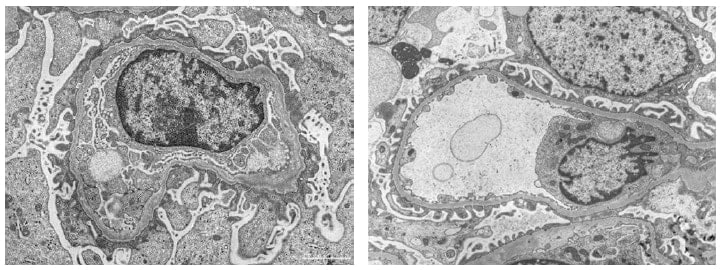

TEM images of renal biopsy specimens from cases of Alport syndrome (left) and thin basement membrane disease (right) are shown here for comparison of typical TEM images of these two pathologies.

Alport syndrome is a hereditary, progressive disease in which characteristic changes occur in the glomerular basement membrane. Similar abnormalities in the glomerular basement membrane can also be seen in thin basement membrane disease. However, in Alport syndrome, these abnormalities can progress to end-stage renal disease in youth, necessitating dialysis. It is therefore essential to distinguish between the two. As described by Dr. Okada, "The two are generally differentiated by conventional immunostaining and TEM and now also by genetic testing, but the results are sometimes inconclusive, and there is a strong possibility that LVSEM will be useful in this regard."